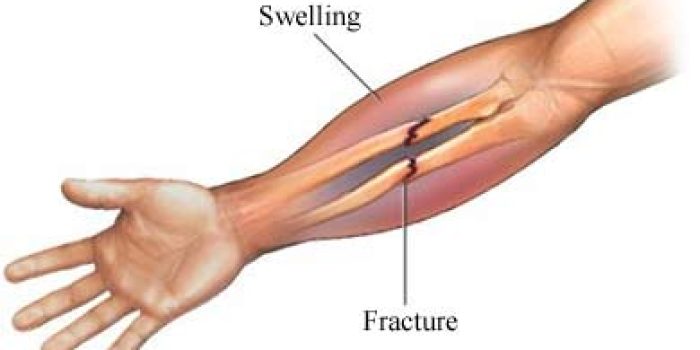

وقتی هر دو استخوان ساعد شکسته شده است شکل ظاهری ساعد بیمار تغییر میابد. ساعد در محل شکستگی خم میشود و گاهی اوقات میتوان نوک تیز استخوان در محل شکستگی را در زیر پوست ساعد لمس کرد. در بعضی موارد نوک تیز استخوان شکسته شده پوست را سوراخ کرده و بیرون میزند و شکستگی را به نوع باز تبدیل میکند.

وقتی شکستگی فقط در یک استخوان ساعد ایجاد شده یا جابجایی کمی دارد معمولا ساعد در محل شکستگی بسرعت متورم و دردناک میشود. در این موارد ممکن است حرکت دادن ساعد موجب برخورد قطعات شکستگی به یکدیگر شده و ایجاد صدا کند که به آن کریپیتاسیون میگویند.